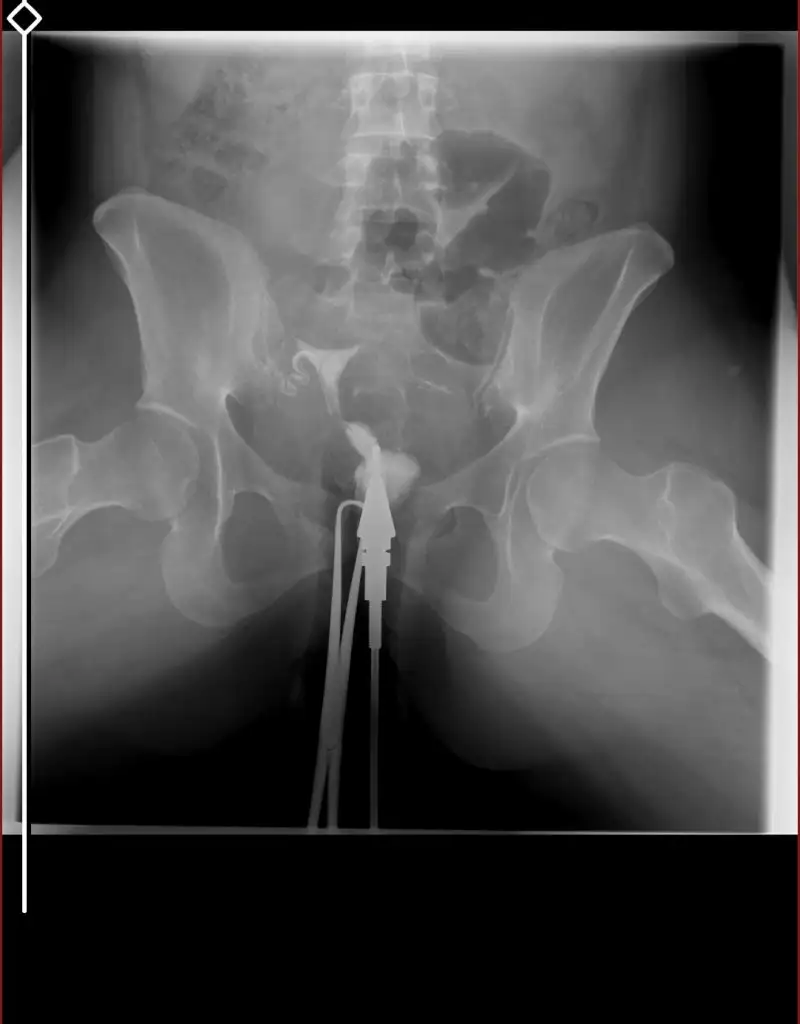

tüp bebek merkezine yönlendirdi . Orada daha detaylı kan tahlili muayene yapıldı adet bitimi hsg çekindim . Çekindiğim gün işlem başında doktor iki tüpün de tıkalı canım dedi ben ağlamaya başladım ağlama sakinleş ilaç ile açmaya çalışacağım eğer olmazsa ameliyat olursun demişti . İşleme 4-5 kez tekrarladık . Sonra iyi kötü bi gidiş oldu . O zaman ki ilgilenen doktora olanları anlattım böyle birşey imkansız tüpler açık o ara kasmışsındır dedi ama hiç kasmadım inanın ki . 6 ay dene olmazsa gel dedi 6 ay sonra gittim o doktor yoktu . Başka doktora geçtim oda sızıntının yeterli olmadığını hala tıkalı olduğunu ve içeriye iyi bir müdahale yapılması gerektiğini söyledi . Ameliyat önerdi . Laparoskopi olacağım ayın 27 sinde . Sonrasında aşılama yapmaya başlıcaz olmazsa